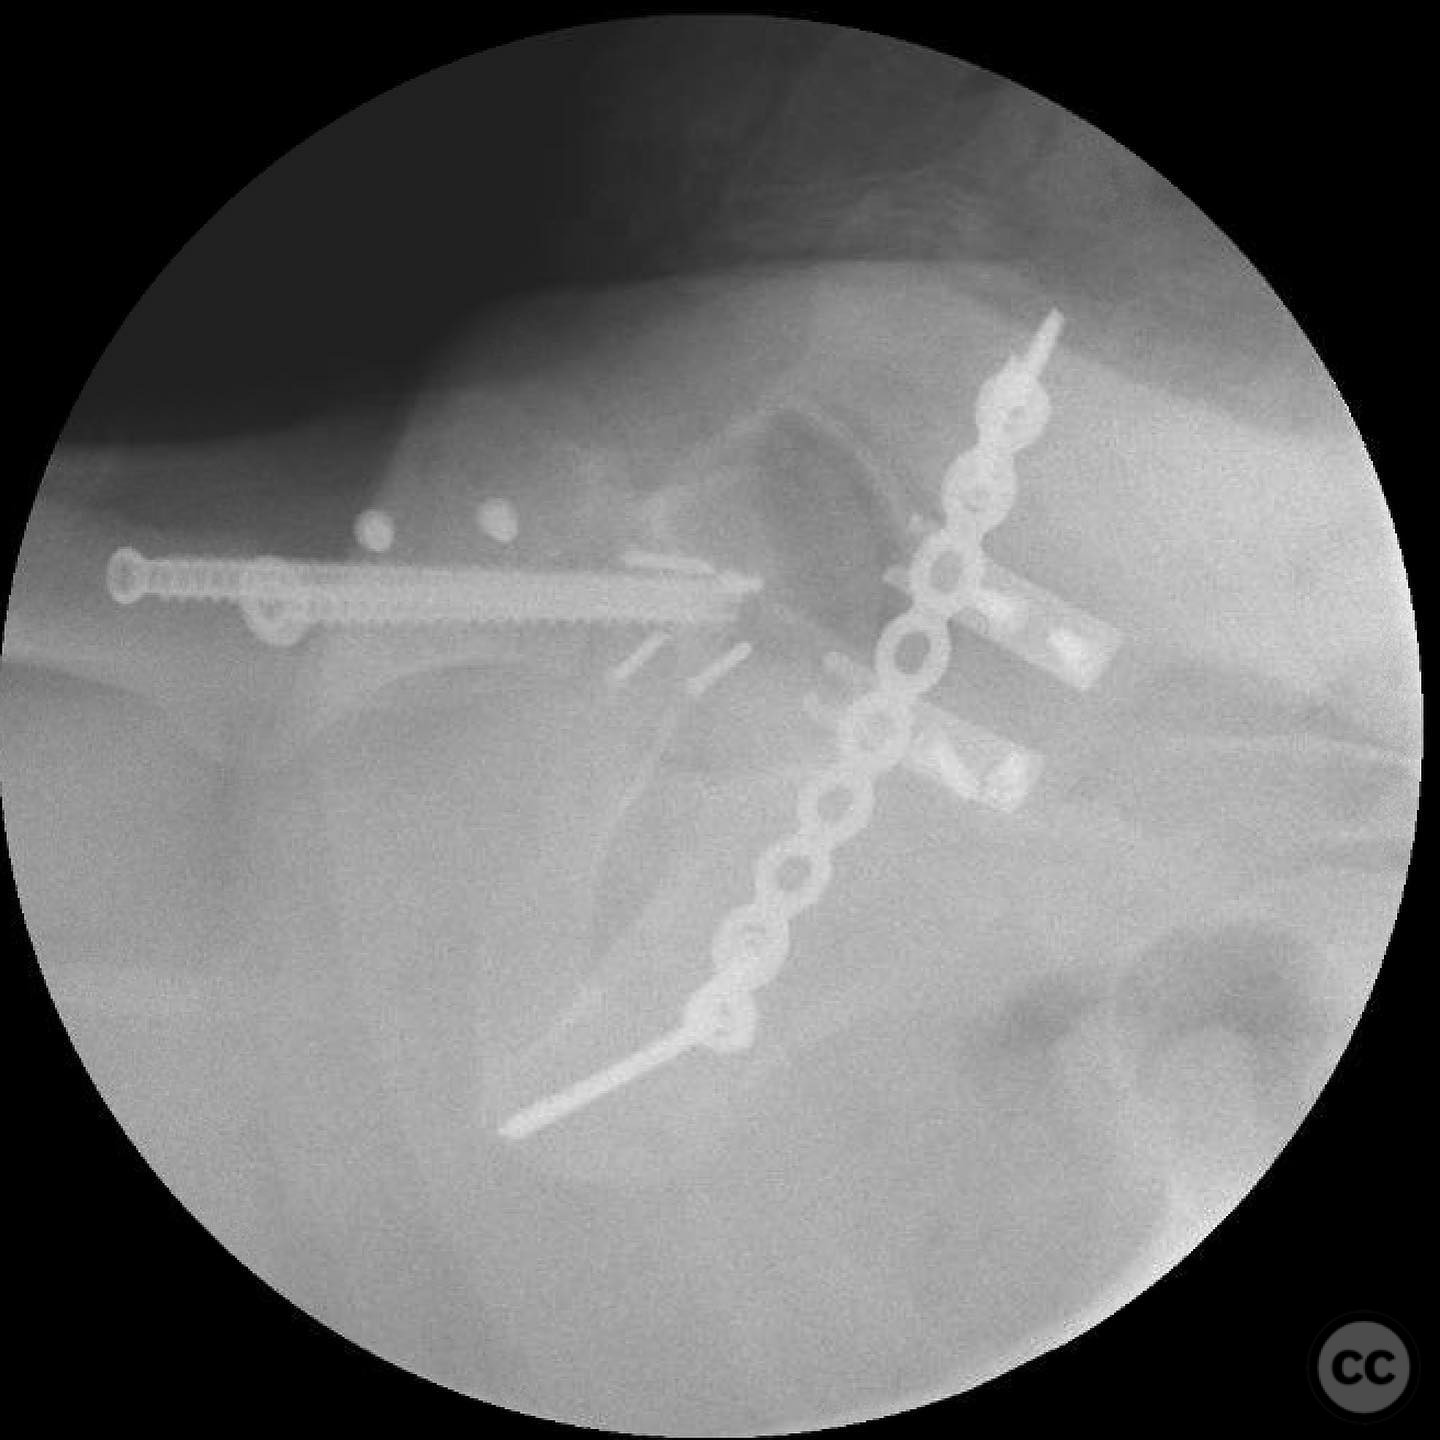

Operative remarks:

The femoral head defect required meticulous reconstruction using a femoral head allograft to restore its round shape. The posterior wall instability was addressed with spring plates and three suture anchors to reattach the capsulolabral complex. The reconstruction aimed to achieve a stable and congruent hip joint.

Orthopaedic implants used:   Femoral head allograft, spring plates, suture anchors.